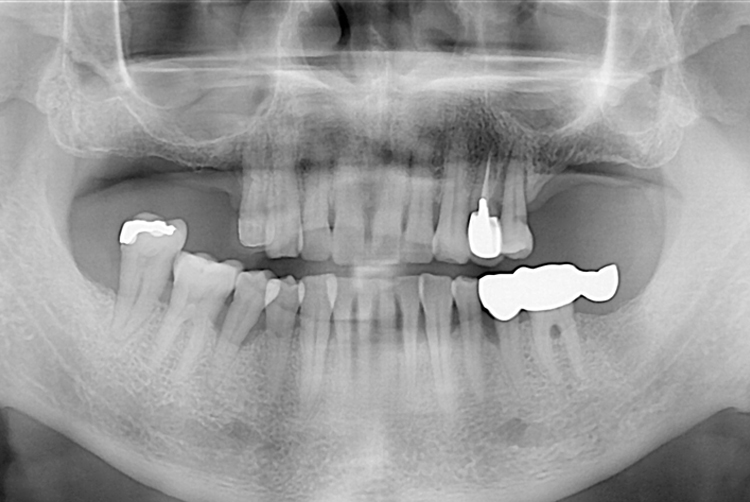

치료전 : 2016-12-02